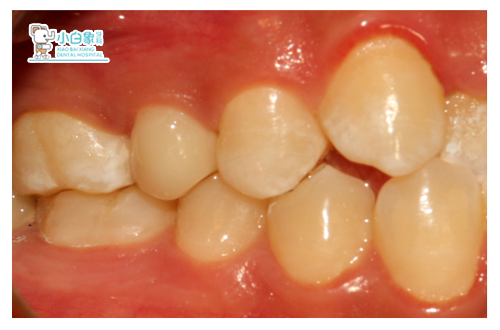

检查:合面及近中缺损达根管口,根管口见充填材料,叩(土),温度测试无反应,牙龈无红肿。

诊断:15无髓牙/慢性根尖炎

治疗计划:15根管治疗+纤维桩+瓷睿刻全冠修复